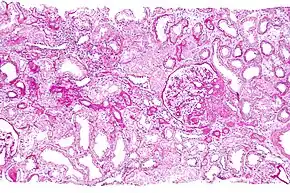

![]() Micrograph showing a renal core biopsy. PAS stain. | |